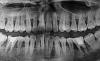

teberda Опубликовано 2 февраля, 2013 Поделиться Опубликовано 2 февраля, 2013 Здравствуйте! Проконсультируете пожалуйста. Вот два снимка, сделанные с разницей в год. Врач рекомендовал срочно делать кюретаж, лоскутную операцию всех зубов, шинирование (пломбирование"шнурком" всех зубов с внутренней стороны как сказал врач). Но не дает гарантии. Мне 26 лет, детей нет. Изучаю сейчас сайты, форумы. Очень мучает вопрос почему это случилось, дело в том, что была большой фанаткой зеленого чая, и где-то недавно прочитала, что он очень негативно влияет на зубы, не уже ли из-за этого? Возможно ли этот процесс остановить каким-либо образом кроме операции? На сколько плачевная ситуация? Как срочно стоит делать операцию? Или Имплантация? Ссылка на комментарий

Solnyshko Опубликовано 2 февраля, 2013 Поделиться Опубликовано 2 февраля, 2013 Здравствуйте! Проконсультируете пожалуйста. Вот два снимка, сделанные с разницей в год. Врач рекомендовал срочно делать кюретаж, лоскутную операцию всех зубов, шинирование (пломбирование"шнурком" всех зубов с внутренней стороны как сказал врач). Но не дает гарантии. Мне 26 лет, детей нет. Изучаю сейчас сайты, форумы. Очень мучает вопрос почему это случилось, дело в том, что была большой фанаткой зеленого чая, и где-то недавно прочитала, что он очень негативно влияет на зубы, не уже ли из-за этого? Возможно ли этот процесс остановить каким-либо образом кроме операции? На сколько плачевная ситуация? Как срочно стоит делать операцию? Или Имплантация? Гарантии ,действительно ,здесь никто не даст.Мысль про чай отбросьте. Провериться нужно у эндокринолога,все ли в порядке со щитовидной железой? диабет? у кардиолога,гастроэнтеролога? Есть ли аутоиммунные заболевания? Наследственность? Постараться выявить причину. Должна быть идеальная гигиена,купить ирригатор, профгигиена не реже раза в полгода. Посев из карманов на микрофлору,может антибиотики придется пропить. И ,конечно лоскутные.. Ссылка на комментарий

Bier Опубликовано 3 февраля, 2013 Поделиться Опубликовано 3 февраля, 2013 Ситуация очень плачевная. Надо думать не то, что об операции, которую надо было делать еще вчера, тут впору подумать о тотальной имплантации.Но прежде общее обследование. Ссылка на комментарий

IvanK Опубликовано 4 февраля, 2013 Поделиться Опубликовано 4 февраля, 2013 +1Обследование.Лоскутные операции + фанатичное отношение к гигиене, в случае, если планируется съемное протезирование. Шинирование сильно усугубит гигиену, что приведет к более быстрой потере менее подвижных зубов...Если есть возможность задумайтесь о тотальной имплантации. Ссылка на комментарий